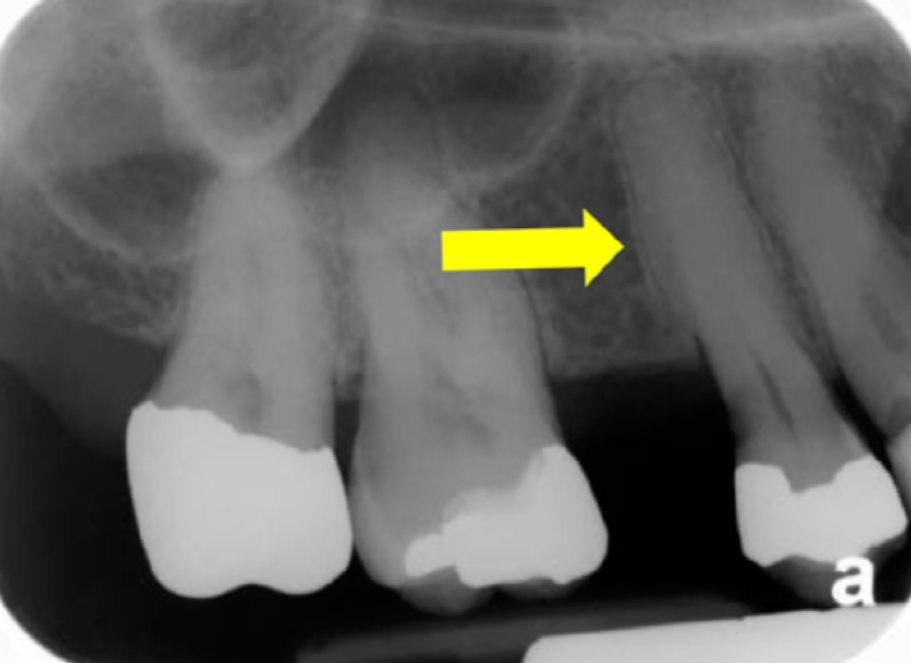

How does cementum appear radiographically?

Appears more radiolucent than either enamel or dentin but more radiopaque than pulp tissue